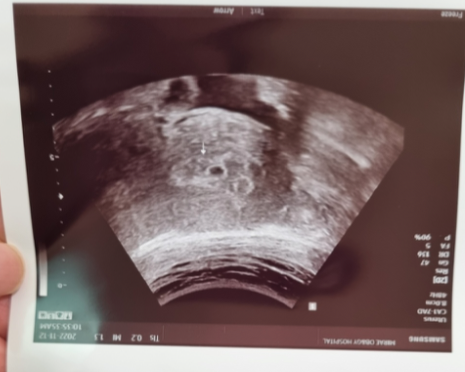

질 초음파 시도

난소가 많이 부어있고 근종도 있어서 잘 안보인다고 배 위로 한번 보자고 하심.

배 위로 꾹 누르시더니

"쌍둥이 괜찮아요?"